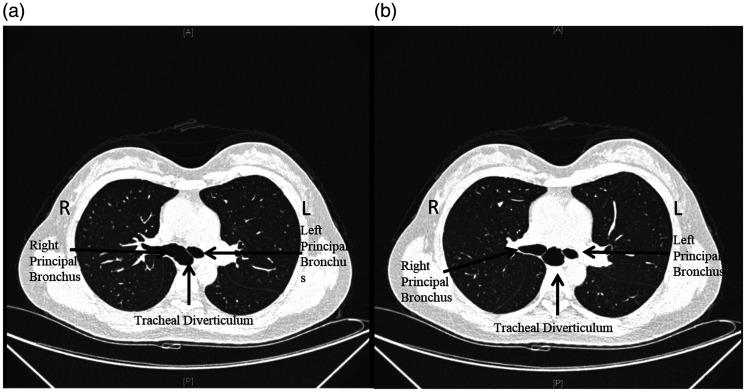

Anesthetic management of thoracoscopic pulmonary wedge resection with a giant tracheal diverticulum in the carina: a case report and review of the literature.

A tracheal diverticulum (TD) is a rare disease that is usually diagnosed as an incidental finding on thoracic computed tomography or bronchoscopy. TDs can be classified as congenital or acquired. In patients undergoing surgery, TDs can result in difficult intubation, difficult ventilation, pneumothorax, and other complications. We herein report a case of anesthetic management of thoracoscopic pulmonary wedge resection in a patient with a giant TD in the carina. Intraoperative double-lumen intubation and single-lung ventilation were challenging to perform. Fiberoptic-guided intubation was helpful, and intraoperative management was tailored to avoid diverticulum rupture. In this report, we also review complications related to TD in surgical patients undergoing mechanical ventilation. Ventilation is one of the most prominent anesthetic challenges. The close collaboration of the entire medical team was a key factor in the successful management of this rare case.